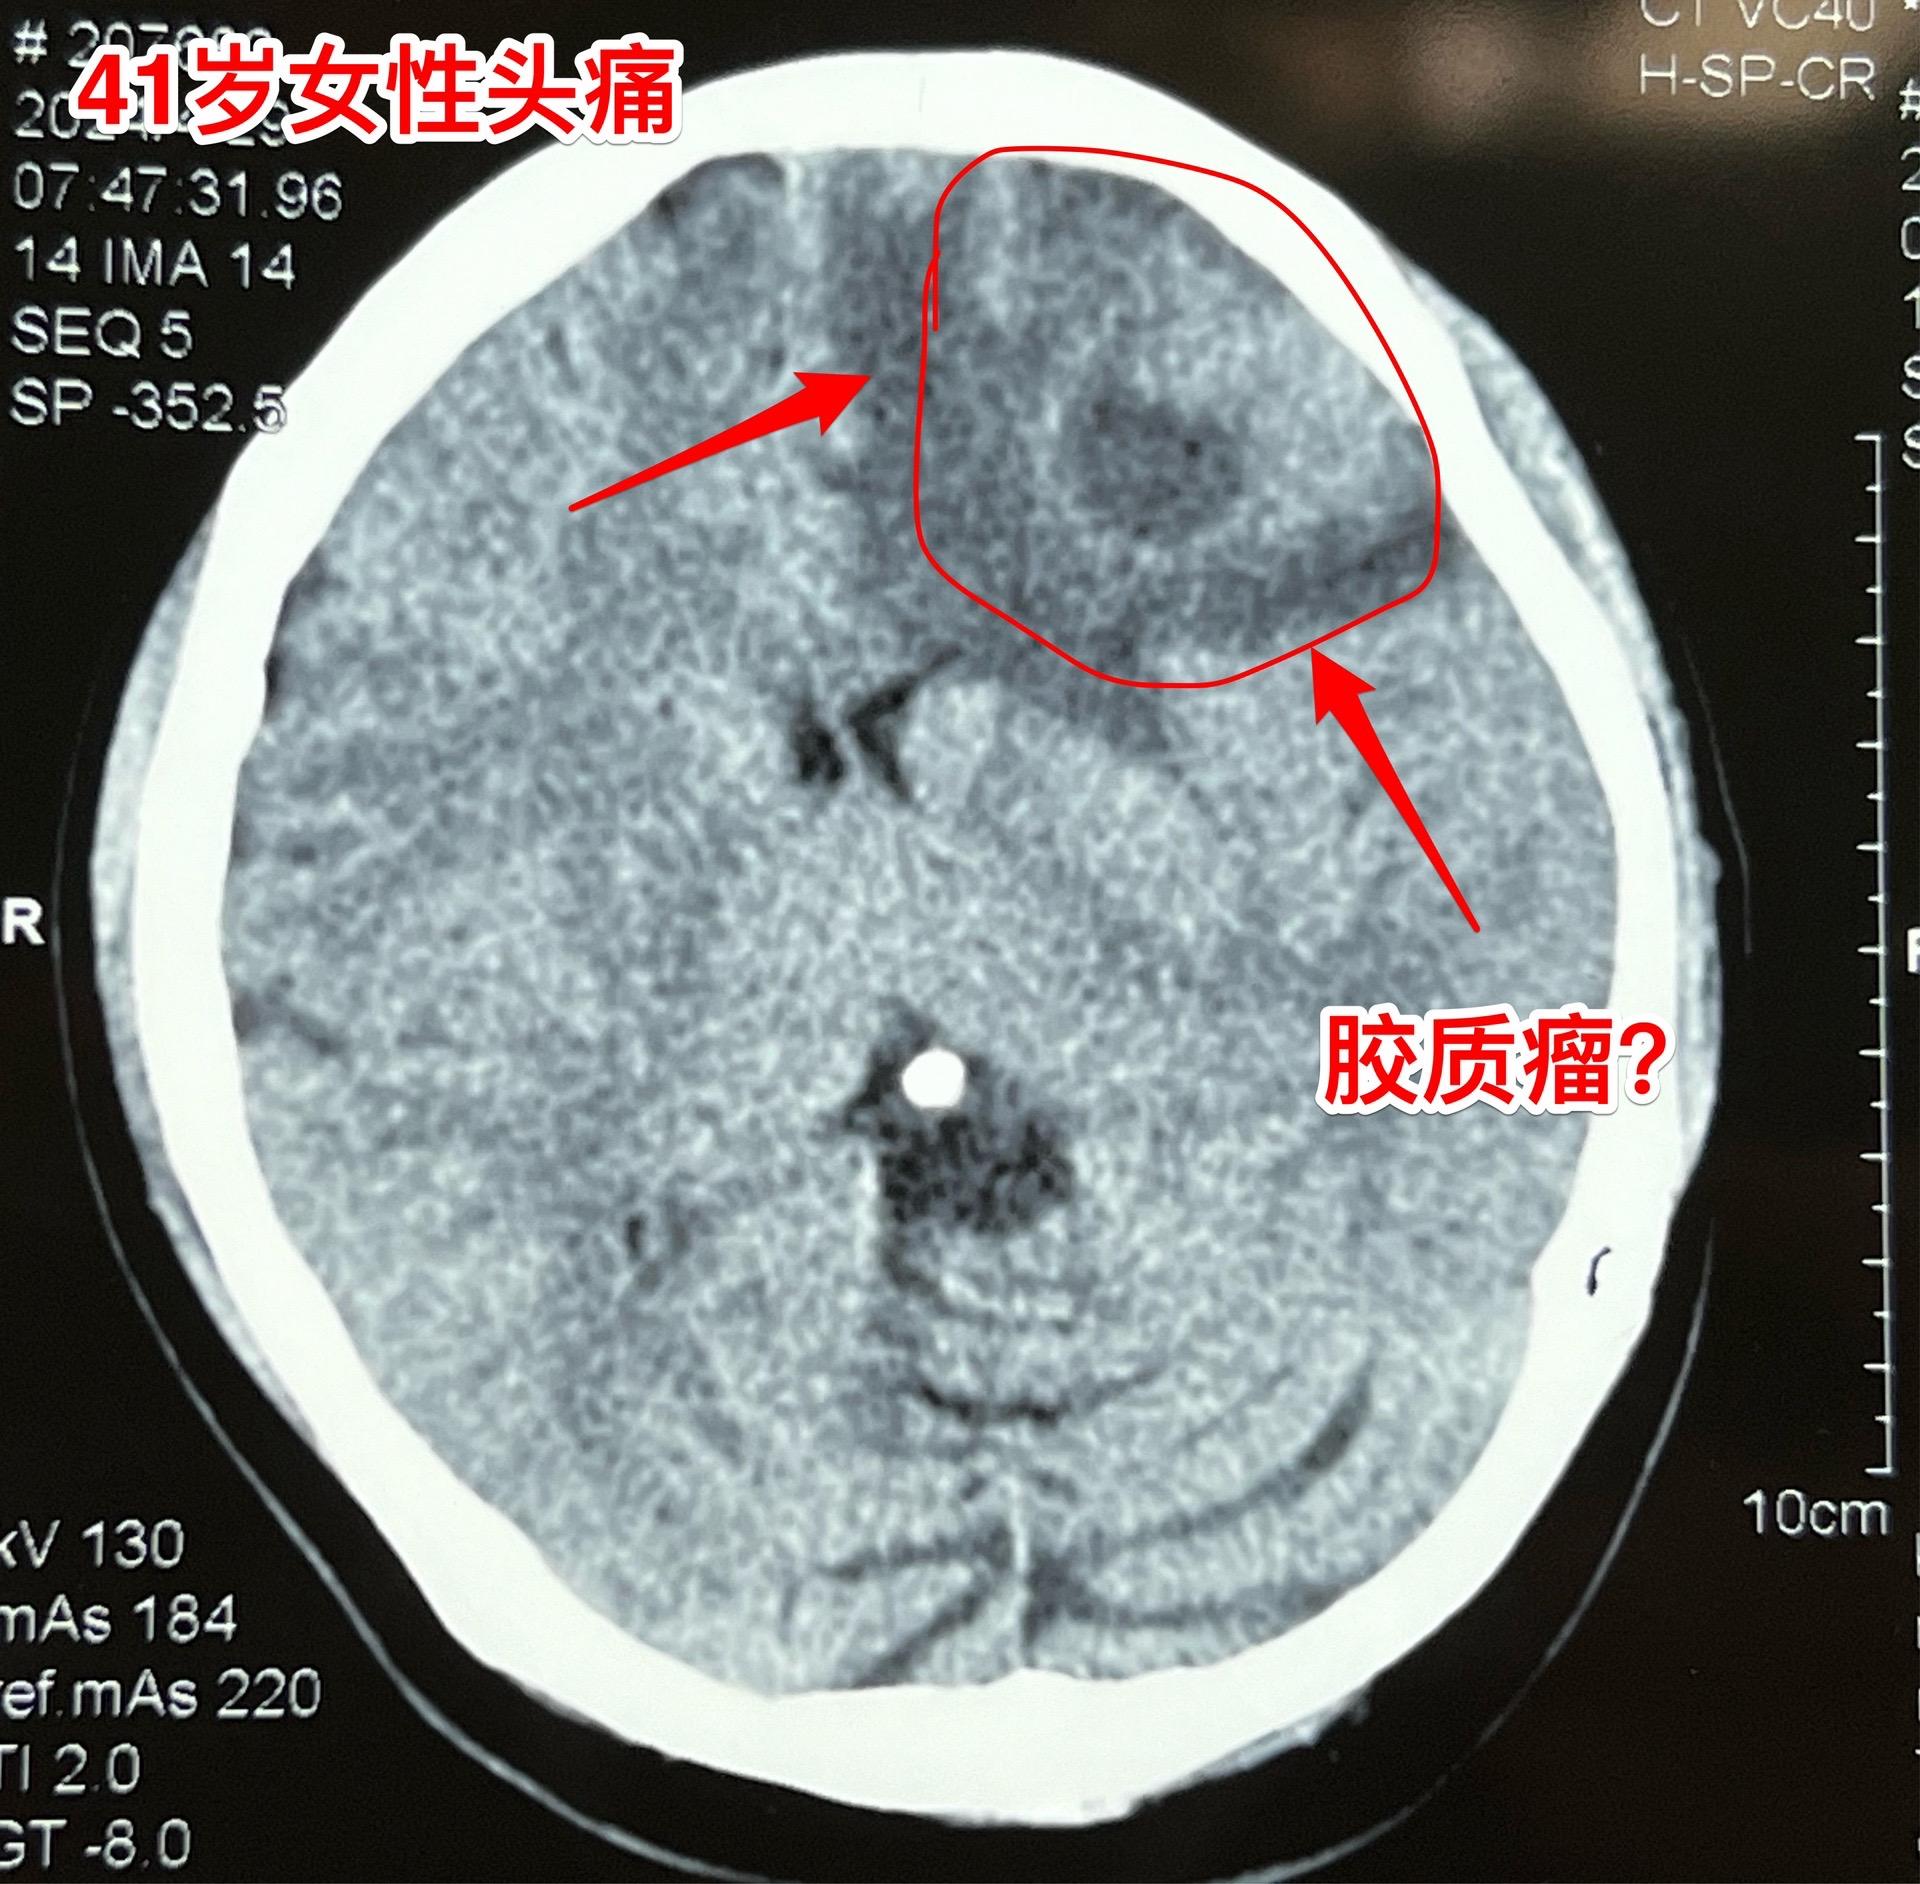

脑肿瘤导致病人头痛,是胶质瘤吗?脑部最常见的肿瘤是胶质瘤。 这个41岁女性病人本身是医务工作者,头痛十天了,4.29到医院去检查脑部CT、磁共振,发现这个肿瘤。肿瘤周围有水肿,脑部受压移位,发现肿瘤后立即到北京来治疗。4.30作了手术,将肿瘤完全切除,手术后病人没有出现失语症状,四肢活动也有力。 术中判断肿瘤为胶质瘤,确诊需要等病理诊断。